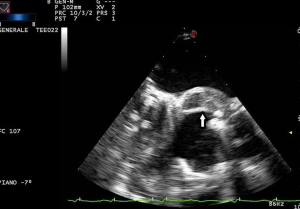

Both transthoracic echocardiography (TTE) and transoesophageal echocardiography (TEE) are the main imaging modalities for diagnosis of IE The European Society of Cardiology (ESC) classify echocardiography as 1B recommendation with echocardiographic results an important Duke criterion (2). Diagnosis based on echocardiographic images has high sensitivity and specificity to detect vegetations, a distinctive sign of IE, particularly if it measures >5 mm (Table 1) and for valve detachment (3). It is however less accurate when it comes to detecting abscesses, aneurysms, pseudoaneurysms, and fistulas. Echocardiography allows the rapid detection of vegetations (Figures 1,2), by measuring the major and minor axes of these, in addition to allowing differentiation from other intracardiac masses, informing the operator on location, mobility (fixed, mobile, oscillating) (Figure 3), echogenicity and potential complications such as the presence of leaks, fistulas, and dehiscences (2,4).

Echocardiography, however, does have several limitations. It is heavily operator dependent and is subject to interoperator variability. In addition, TTE is dependent on having satisfactory imaging windows which are often patient dependent with some having poorly echogenic chests. It is less sensitive for smaller vegetations measuring <5 mm (4). In the elderly, bulky calcific deposits on structures may also make image interpretation difficult. In patients with prosthetic valves, acoustic shadowing by the metallic component of prosthetic valves (on Left Ventricular Outflow Tract in aortic and on Left Atrium in mitral prostheses) may also contribute to its lower sensitivity and specificity (4,5). Some of these patients may also have a submammary prosthesis, which may affect the imaging windows, thereby reducing the sensitivity and specificity of this modality. Echocardiography also is of limited value in evaluating extracardiac lesions and may sometimes lead to delays in detecting intracardiac lesions. The diagnosis of abscesses (Figure 3) can be challenging for echocardiographers with lower sensitivity and specificity (Tables 2,3).